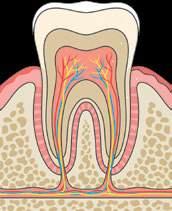

Будова й функції

Людина, як і

ссавці,

диференційовані зуби: різні за формою і функціями (мал. 19.4, с. 95). Різці мають гострий край, яким ми відкушуємо їжу. Ікла допомагають розколювати та відривати шматки їжі. Малі корінні зуби (премоляри) подрібнюють їжу, великі корінні зуби (моляри) виконують основну роботу з її пережовування або розтирання. Перші зуби молочні з’являються

руйнуються під дією органічних кислот, які виділяються численними бактеріями ротової порожнини. Ці бактерії живляться залишками нашої їжі. Карієс виникає через недостатню

гігієну порожнини рота, переважання в раціоні м’якої їжі й вуглеводів. Розвиток карієсу

спричиняє нестача мінералів і вітамінів, які беруть участь у формуванні твердих тканин зубів: Кальцію, Флуору, Фосфору, вітаміну С та інших. До ушкодження емалі зубів також

призводить вживання гарячих, холодних чи

кислих напоїв. Руйнування зуба відбувається

внаслідок бактеріальної інфекції його тканин. X Правила профілактики